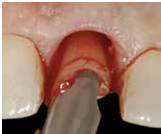

2) 以不翻瓣,無傷害的方式移除牙齒: 先以15c刀片切開supracrestal fiber, 必要時切割牙齒 (fig 8,9)

3)以surgical curette或bur清乾淨齒槽窩, 檢視齒槽窩壁; 特別留意齒槽窩必須有完整的頰側骨壁(不低於free gingival margin 4mm)

(Fig 7,8,9)